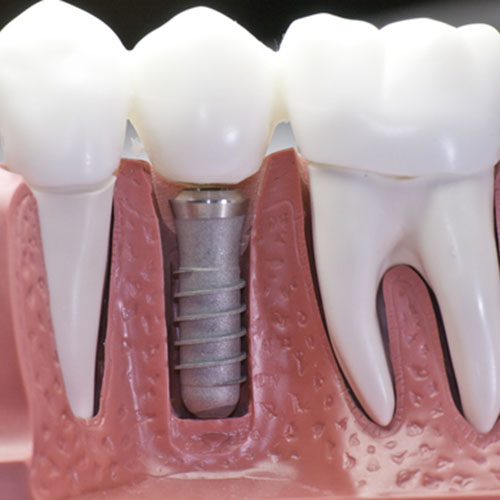

インプラント治療とは、歯が失われてしまった部分に人工の歯を埋入する治療のことです。人工の歯根を顎の骨の中に埋め込み、その上に人工の歯を固定します。 入れ歯やブリッジと異なり隣の歯を削って負担をかけることもありませんし、自分の歯と同じような感覚で強い力で違和感なく噛むことができるようになります。

お口の中が清潔で炎症のない状態であることが確認したうえで、治療を開始します。 局部麻酔を行ったあと、顎の骨にインプラントを埋め込みます。このインプラントが新しい歯の土台となります。

インプラントが顎の骨と結合したら、インプラントの上にアバットメントを連結して人工の歯(上部構造)を装着する準備をします。

インプラントのヘッドに人工の歯(上部構造)を装着します。これでインプラントを装着する治療が終わります。